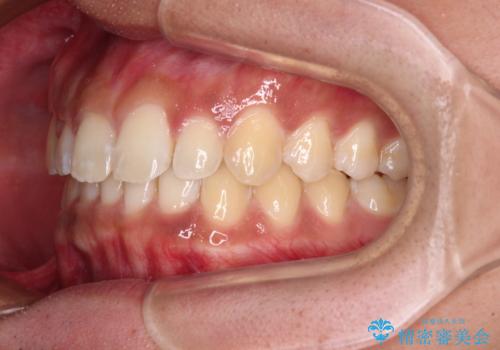

デコボコとディープバイトを治したい インビザラインによる矯正治療

- 前歯のデコボコや隙間と深い咬み合わせ(ディープバイト)を気にして来院された患者様です。

インビザラインによる上下歯列の側方拡大と後方移動、IPR(歯と歯の間を削る)にるスペースの獲得により、デコボコとディープバイトを改善することとしました。

気になっていたデコボコや隙間は改善し、きれいな歯列に整えることができました。

咬合力が非常に強い方であったため、これ以上のディープバイトの改善は困難となりました。